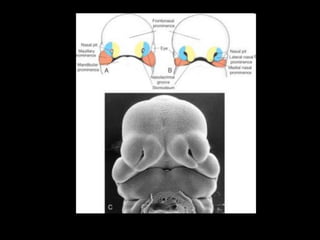

Embryology

• Formation of the lip and palate takes place

between the 5th and 10th week of fetal life

Failure of fusion of medial nasal process and

maxillary process results in a cleft lip

• 4.

Embryology • Formation ofthe lip and palate takes place between the 5th and 10th week of fetal life

• 5.

Embryology Failure of fusionof medial nasal process and maxillary process results in a cleft lip